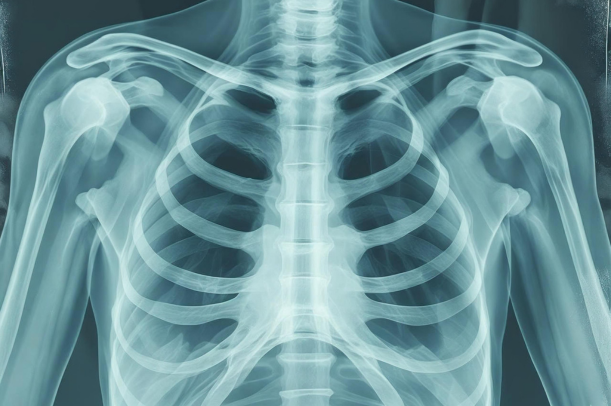

一方で、強い痛みや腫れ、押すと響くような圧痛を感じるケースが多く、レントゲンなどの検査をしなければ発見が難しい場合もあるようです。

その後、患部の腫れや圧痛、可動域などを確認する触診を行い、必要に応じてX線(レントゲン)検査を実施します。

もしX線で異常が確認しづらい場合は、CTやMRIでより細かい骨の状態を確認することもあるそうです。